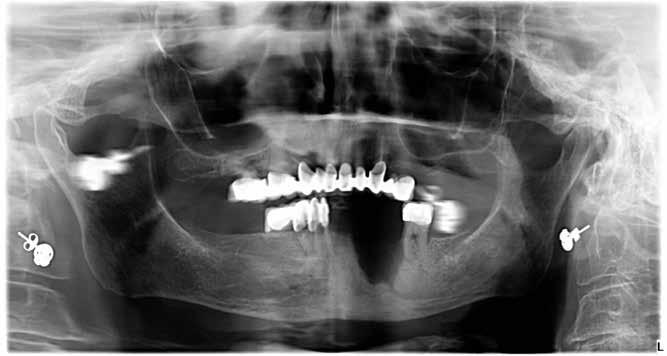

Ebben a cikkben egy 16 éves lánypáciens esetét szeretném bemutatni (1–7. képek)

A Pitts21-es fix készülékes kezelés során a harapásemelőket a felső nagyőrlő fogakra ragasztottuk, hogy a felső molárisok intrúziójával segítsék a harapás zárását (8. kép) Ún. keresztharapásos, majd később normál class 2-es gumihúzással (9–10. képek), továbbá az elülső fogakon alkalmazott ún. Rainbow harapás-záró gumihúzással (11. kép) korrigáltuk a jobb oldali teljes premolárisnyi distal-harapást, valamint az elülső nyitott harapást.